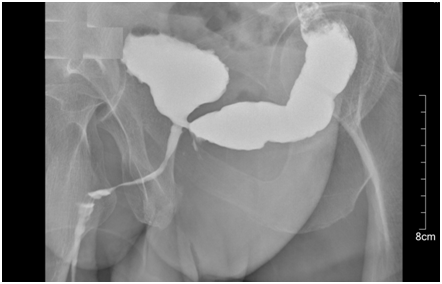

The diagnosis is composed by the clinical signs mentioned above and a radiological image, that frequently consist on a cystography (Figure 1). As first attempt to solve the fistula, the patients undergoes a longer urinary catheterization, medical therapy and closure of the rectal wall damage. Only up to 46% of RUF.5 obtain the closure with this so called "conservative treatment". In case of recurrent RUF, the first step is the reduction of the fistula "flow" through a double diversion: faecal diversion (colostomy) and urethral catheterization. At this point multiple approaches and surgical techniques have been proposed. Hechenbleikner EM et al.6 has shown that patients affected by RUF undergoes up to 4 categories of repair with a 87,5% rate of fistula closure and with more than 10% rate of permanent fecal and/or urinary diversion. Techniques available can divided in 2 groups: trans-abdominal (open or laparoscopic) and perineal. In the trans-abdominal group the linkage closure is obtained suturing the rectal wall lesion with or without omentum patch, clips or glue. Unfortunately results are poor with low rate of fistula solution.

Figure 1 Cystography.